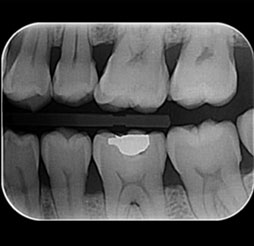

03

拍摄口腔内部

Oral Photography / Bite-Wing Radiography / Periapical Radiograph

-

[ 拍摄口腔内部 ]

从前牙到后牙, 临街牙齿部位,

牙齿平面的蛀牙及治疗状态都能扩大确认 . -

[ 拍摄咬翼 ]

为了更仔细确认牙齿头部拍摄X光片,

有效预防不能早期发现的牙齿面蛀牙 . -

[ 拍摄牙根 ]

* 需要时拍摄为了更仔细, 精密的检查问题牙齿拍摄X光片,

牙根底部炎症, 牙齿根管状态, 一般蛀牙等2次蛀牙都能确认 .